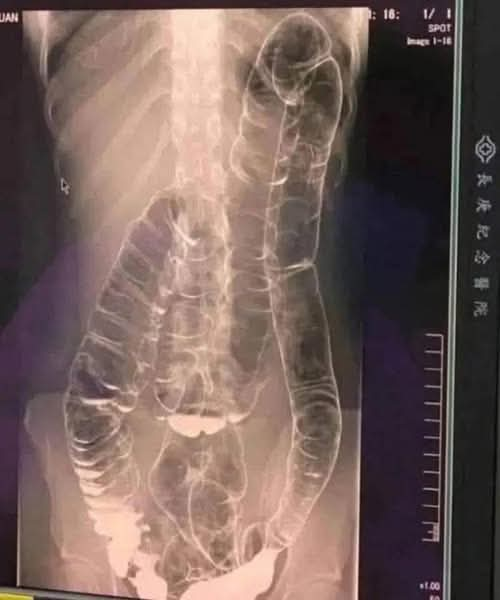

Een verzadigde dikke darm: wanneer uw lichaam alarm slaat

Wie heeft er niet last van constipatie? Dit probleem, vaak als triviaal beschouwd, kan een ware nachtmerrie worden als het chronisch wordt. Dit is precies wat een jonge vrouw overkwam bij wie de overbelaste dikke darm gevaarlijk vergrootte. Dus hoe kunnen we voorkomen dat deze spijsverteringsstoornis verergert? Verzadigde dikke darm Bij een onregelmatige stoelgang hopen … Lire plus